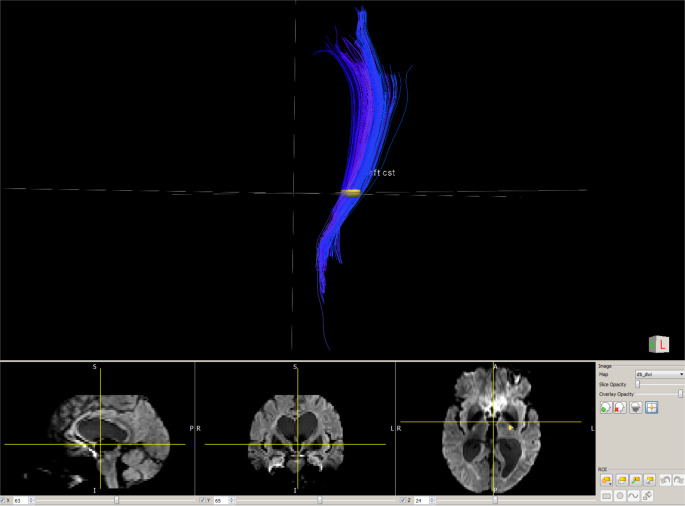

Multiple sclerosis (MS) is a central nervous system disease involving gray and white matters. Transcranial magnetic stimulation (TMS) and magnetic resonance imaging (MRI) could help identify potential markers of disease evolution, disability, and treatment response. This work evaluates the relationship between intracortical inhibition and facilitation, motor cortex lesions, and corticospinal tract (CST) integrity. Consecutive adult patients with progressive MS were included. Sociodemographic and clinical data were collected. MRI was acquired to assess primary motor cortex lesions (double inversion and phase-sensitive inversion recovery) and CST integrity (diffusion tensor imaging). TMS outcomes were obtained: motor evoked potentials (MEP) latency, resting motor threshold, short-interval intracortical facilitation (ICF) and inhibition. Correlation analysis was performed. Twenty-five patients completed the study (13 females, age: 55.60 ± 11.49 years, Expanded Disability Status Score: 6.00 ± 1.25). Inverse correlations were found between ICF mean and each of CST radial diffusivity (RD) (ρ =-0.56; p < 0.01), CST apparent diffusion coefficient (ADC) (ρ=-0.44; p = 0.03), and disease duration (ρ=-0.46; p = 0.02). MEP latencies were directly correlated with disability scores (ρ = 0.55; p < 0.01). High ADC/RD and low ICF have been previously reported in patients with MS. While the former could reflect structural damage of the CST, the latter could hint towards an aberrant synaptic transmission as well as a depletion of facilitatory compensatory mechanisms that helps overcoming functional decline. The findings suggest concomitant structural and functional abnormalities at later disease stages that would be accompanied with a heightened disability. The results should be interpreted with caution mainly because of the small sample size that precludes further comparisons (e.g., treated vs. untreated patients, primary vs. secondary progressive MS). The role of these outcomes as potential MS biomarkers merit to be further explored.

Abstract Image